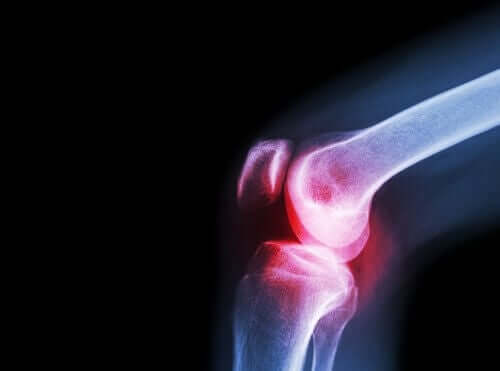

Un altro sintomo tipico del lupus eritematoso sistemico è il dolore articolare a causa dell’artrite che accompagna la reazione autoimmune del corpo. Si verificano episodi acuti di dolore articolare, che si alternano a periodi di assenza del dolore ad altri molto dolorosi.